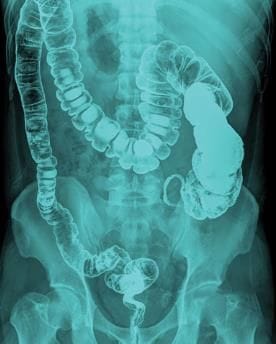

Barium Studies

Barium sulfate is used for gastrointestinal tract (GIT) evaluation due to its inert nature and lack of absorption, with mucosal coating aiding in assessing mucosal details.

Types:

- Barium Swallow: For dysphagia to rule out stricture or mass, largely replaced by endoscopy; now used for motility disorders.

- Barium Meal: For abdominal pain to rule out gastric/duodenal ulcers, replaced by endoscopy.

- Small Bowel Follow-Through: For diarrhea or constipation to rule out Crohn's disease or other small bowel pathologies, replaced by barium enteroclysis (small bowel enema) or CT enterography.

- Barium Enema: For rectal bleeding to rule out polyps or masses, sometimes replaced by CT virtual colonoscopy.